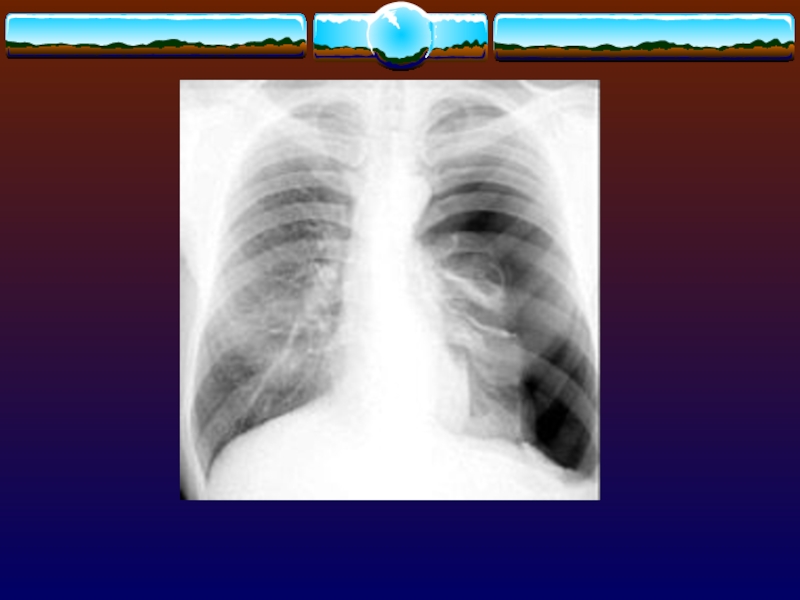

Слайд 6Рентгенография грудной клетки

Проводят, чтобы исключить сопутствующий гемо- или пнемоторакс

В

50% случаепереломы рёбер остаются незамеченными, за исключением переломов верхних рёбер

Используют

косые проекции, что позволяет увеличить информативность метода при диагностике переломов рёбер

Рентгенография грудной клетки Проводят, чтобы исключить сопутствующий гемо- или пнемотораксВ 50% случаепереломы рёбер остаются незамеченными, за исключением

При рентгенографии - плотный

лёгочный инфильтрат над поврежденной областью, но определяется только через 12-24

ч после повреждения.

Степень прогрессирования клинических и рентгенологических данных соответствует тяжести поражения.

При КТ диагноз возможно подтвердить раньше, чем при обзорной рентгенография.